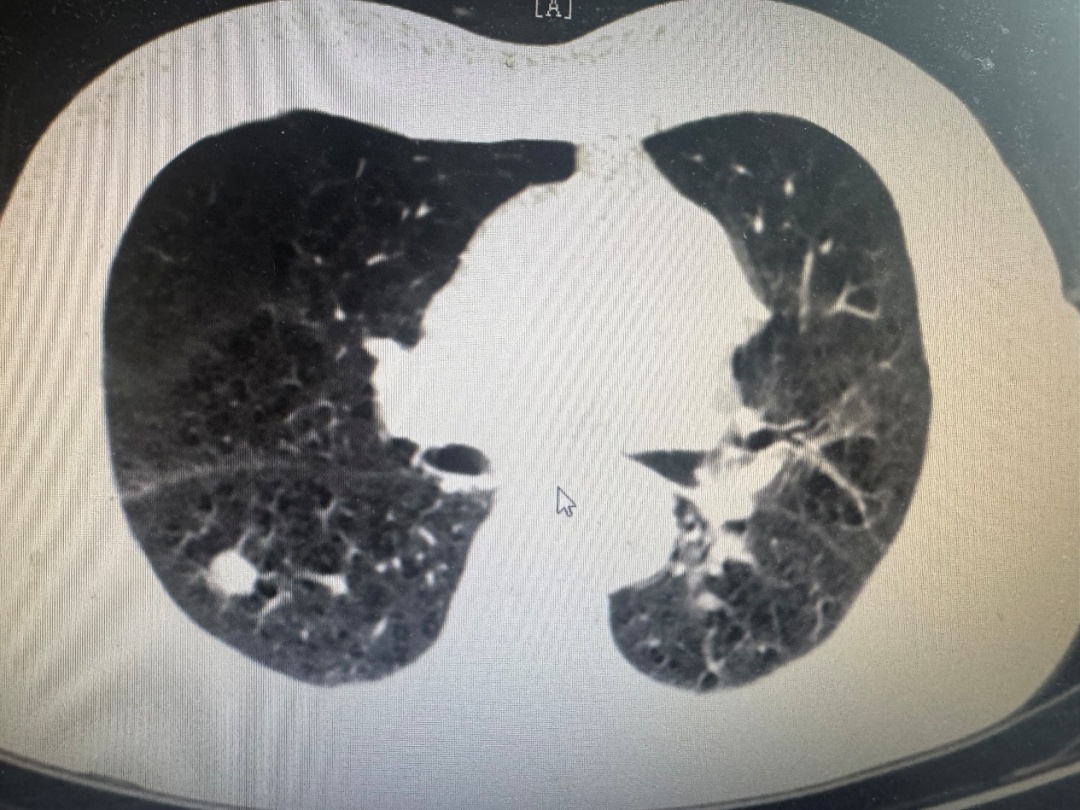

然而,手术之路布满荆棘。陈老伯不仅高龄,还长期受慢性阻塞性肺疾病、冠心病、脑梗后遗症等多种疾病困扰。入院评估结果更令人担忧:肺功能严重受损,爬两层楼即气喘吁吁,屏气时间仅15秒,肺功能关键指标仅达预计值的60%。PET-CT检查提示双肺结节高度怀疑恶性可能,冠脉CTA提示多处冠脉重度狭窄。这些因素交织,使他对麻醉和手术的耐受能力极低,传统手术风险巨大,一度被视为“手术禁区”。

术中发现患者右侧胸腔粘连严重,视野暴露困难。团队凭借丰富的胸腔镜手术经验,耐心细致地进行粘连松解,成功建立清晰操作空间。随后,精准定位并完整切除了右肺上叶后段及下叶背段的两枚肺癌结节。术中快速冰冻病理检查证实:两处均为“浸润性腺癌”。手术过程顺利,出血量少。